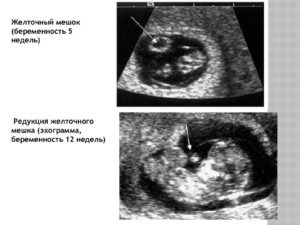

Специальный орган, формирующийся на начальных стадиях беременности, и со временем атрофирующийся до конца третьего триместра, называется желточный мешочек. Он напоминает форму кольца и имеет тонкие стенки. Размеры желточного мешка с пятой по двенадцатую неделю должны быть 3-6 миллиметров в диаметре.

Желточной мешок при беременности начинает визуализироваться с 5,5 недели. При нормально развивающейся беременности на сроке 5-10 недель размер желточного мешка должн быть меньше 5,5 миллиметров.

С 8 по 12 недели беременности размер желточного мешка должен быть более 2 миллиметров.

Начиная с 6 недели его хорошо видно на УЗИ.

На 6–10 неделе беременности диаметр мешочка не должен превышать 5,5 мм. На сроке 8–12 недель он не должен быть больше 2 мм. Начиная с 12–13 недели пузырь уже невозможно идентифицировать с помощью ультразвука.

Редукция желточного мешка

Однако бывают случаи, когда редукция (распад) его задерживается, и происходит его кистозное перерождение. Этот факт не должен вызывать большого беспокойства при условии, что все остальные показатели скринингового УЗИ оказались в норме.